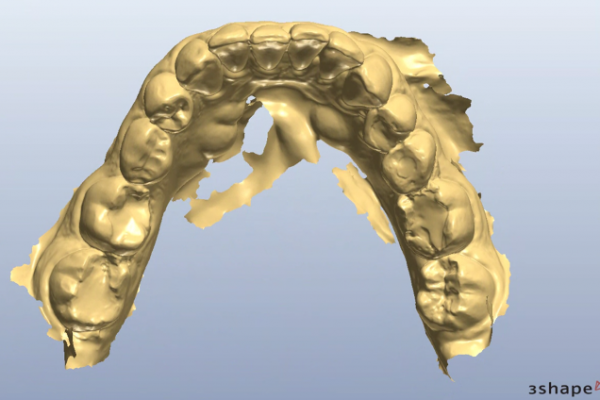

So, prior to a hygiene work up, the patient was then assessed from an orthodontic perspective for short-term pre-restorative orthodontics. This was to improve tooth position (Figures 2 a,b and c) and allow for a less destructive tooth preparation.